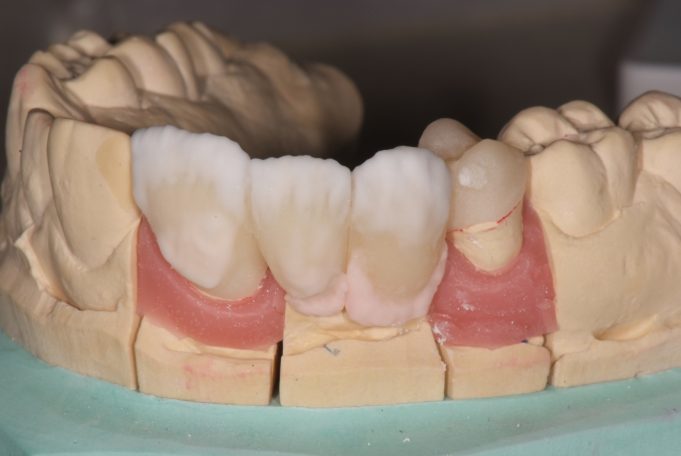

Vollkeramische Teilungsbrücke zum Ersatz der fehlenden Zähne und minimalinvasiver Verankerung.